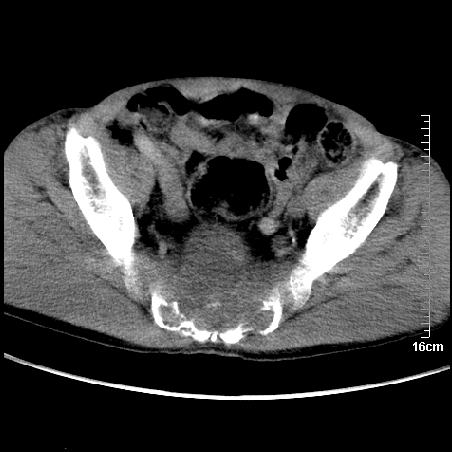

标题: CT16886:骶尾部占位:1.脊索瘤?2.巨细胞瘤? [打印本页]

标题: CT16886:骶尾部占位:1.脊索瘤?2.巨细胞瘤?

增强:

1、骶尾部巨大软组织肿块,部分骶尾骨以被软组织肿块代替,呈不规则侵蚀;病变突向盆腔内;增强扫描病变呈不均质强化;首先考虑脊索瘤。不支持的一点就是病变内无钙化。

2、发生于骶尾椎者须与骨巨细胞瘤鉴别,骨巨细胞瘤一般发在上疗骶椎,肿瘤内无钙化,一般无侵袭性生长的表现。